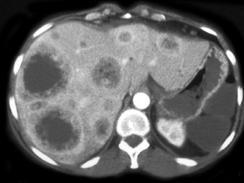

女,65岁,食管癌术后2年,CT检查如图,应诊断为 ( )A、肝囊肿B、肝结核C、肝转移瘤D、肝棘球蚴病E、肝脓肿

问题 女,65岁,食管癌术后2年,CT检查如图,应诊断为 ( )

选项 A、肝囊肿 B、肝结核 C、肝转移瘤 D、肝棘球蚴病 E、肝脓肿

答案 C